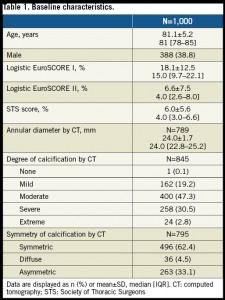

対象:75歳以上の重症ASでheart teamによりTAVIが適当と考えられた患者1000名

1/3の患者に偏在性や重度の石灰化がCTにより確認された。